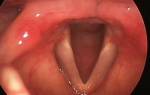

В стационаре, пациенту можно сделать ларингоскопию (прямую и непрямую), бронхоскопию.

Другие эндоскопические методы, с помощью которых можно определить степень поражения, причину патологического состояния, ширину голосовой щели.